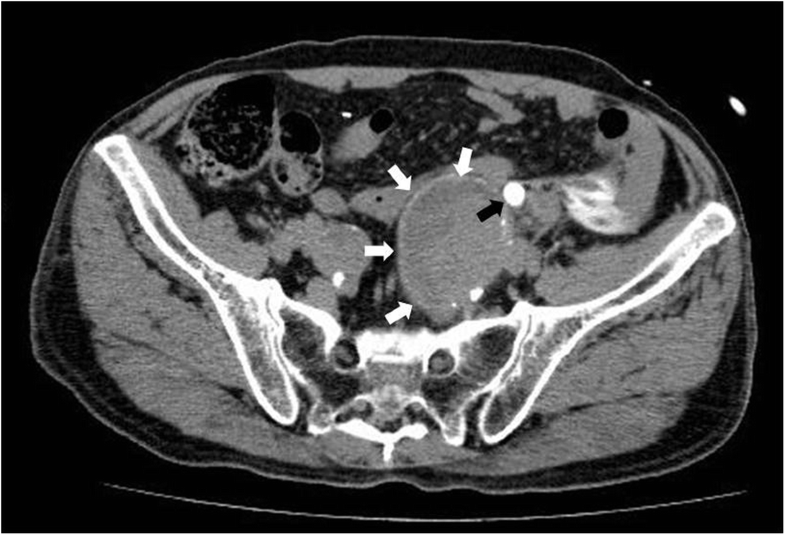

From www.researchgate.net

Ureteral rupture with urinary extravasation (arrow head) on the delayed... Download Scientific Can A Ureter Burst Ureteral obstruction is a blockage in one or both of your ureters that prevents pee from flowing into your bladder. Ureteral stents are temporary devices to prevent or treat urinary tract obstruction, but they can cause problems if left in place too long. Blood clots in urine, or hematuria, can be caused by various factors, such as exercise, injury, medications,. Can A Ureter Burst.

From www.eurorad.org

Spontaneous ureteral rupture An unusual cause of acute abdomen Eurorad Can A Ureter Burst Urinary retention is when your bladder doesn’t empty when you pee. Ureteral obstruction is a blockage in one or both of your ureters that prevents pee from flowing into your bladder. Learn about what causes blockage of the tubes that carry urine from the kidneys to the bladder, tests you might need and how the. Blood clots in urine, or. Can A Ureter Burst.